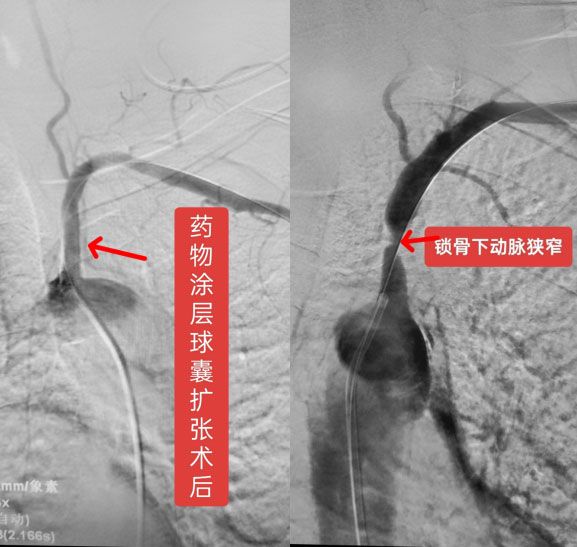

近日,血管介入科王伟迪主任、郭兆阳医师在我院介入手术室护技配合下为一位锁骨下动脉狭窄盗血患者实施药物涂层球囊扩张成型术,获得满意效果。这也是我院药物涂层球囊首次应用于锁骨下动脉狭窄病变。